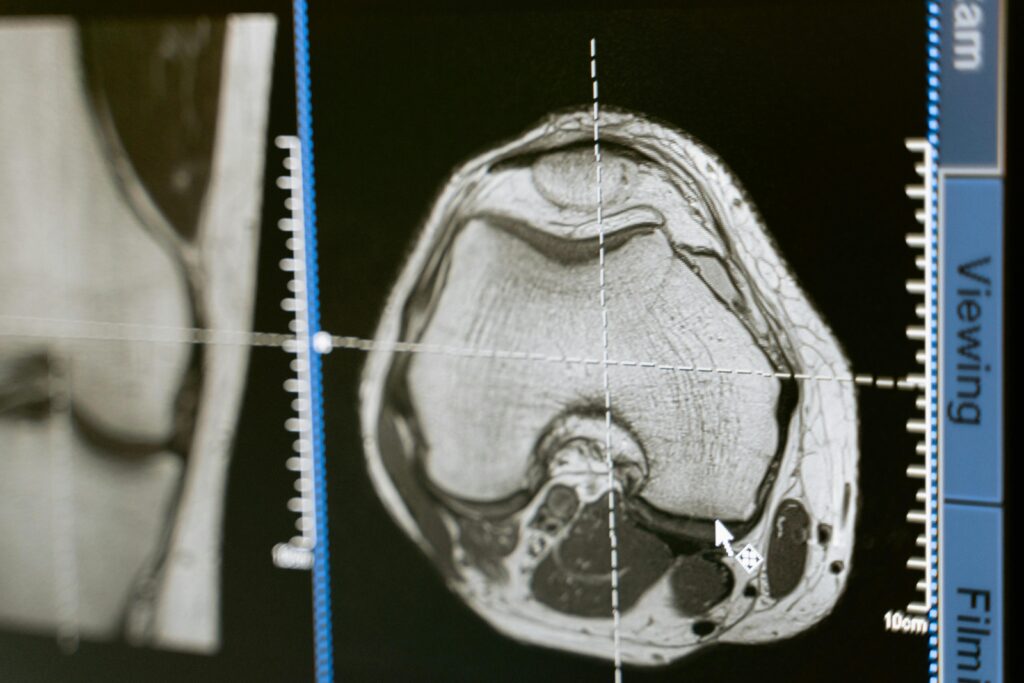

Joint and Musculoskeletal Injuries

Orthopedic specialists often recommend an MRI scan to diagnose ligament tears, muscle injuries, cartilage damage, or joint abnormalities.

Musculoskeletal MRI

This MRI scan evaluates joints, muscles, ligaments, and bones to identify injuries or degenerative conditions.